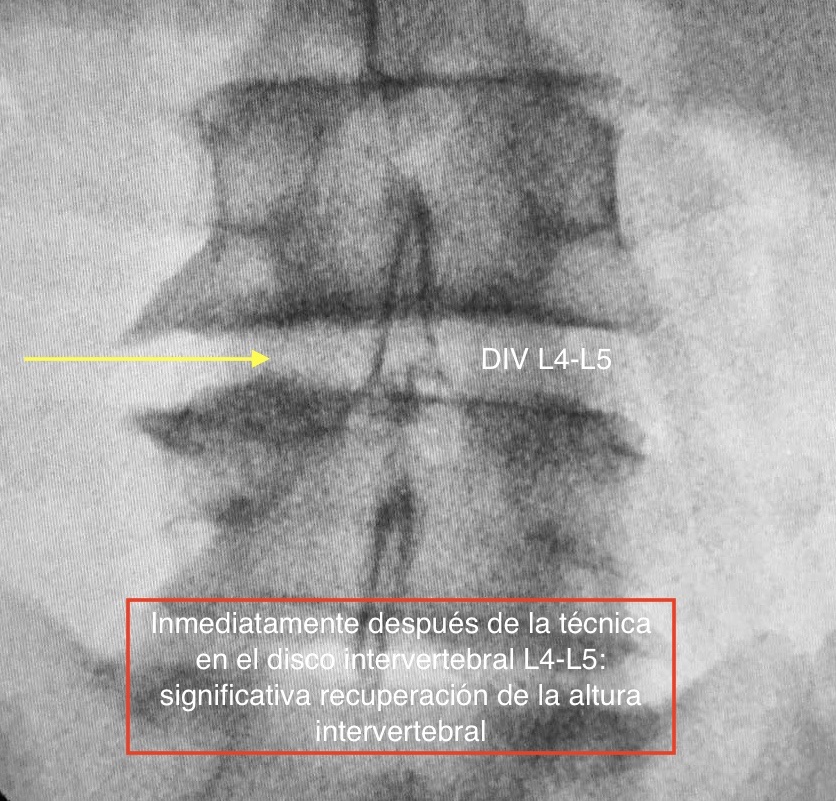

La TERÀPIA REGENERATIVA NEUROESPINAL, desenvolupada per l'equip de Neurocirurgia de la Clínica del Remei (COT- Neurocirurgia Remei) i dirigida per la Dra. Ivón González Valcárcel, és una Intervenció nova i mínimament invasiva exempta de reaccions adverses, avalada per evidència científica, que utilitza la biotecnologia. Ens brinda beneficis immediats en el control del Dolor Lumbar, així com ofereix efectivitat en revertir la cascada degenerativa, amb la conseqüent REPARACIÓ i REGENERACIÓ del disc intervertebral i altres teixits afectats.

Els factors de creixement plaquetaris són proteïnes que es troben en la nostra pròpia sang, exercint importants efectes biològics. Mitjançant aquesta revolucionària tècnica, som capaços de activar-los, concentrar-los i infiltrar amb alta precisió a la zona danyada per la patologia degenerativa. Així participaran directament en la regulació del DOLOR i en la REGENERACIÓ, mitjançant l'estimulació de funcions que donen lloc a la millora significativa o, fins i tot, a la desaparició dels símptomes amb ràpid retorn a l'activitat física quotidiana, amb la qual cosa és una excel·lent alternativa a la cirurgia convencional en molts dels casos